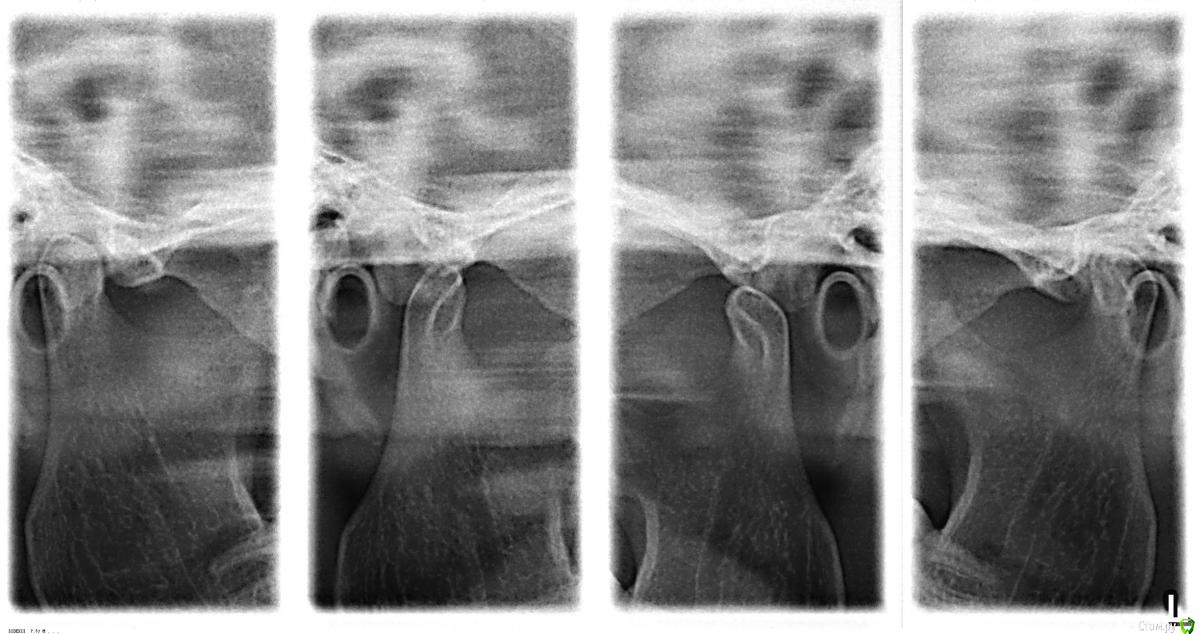

ЗЫ. Снимок ВНЧС (по просьбе доктора) сделан в "неудобном" положении смыкания.

-когда делали снимок с открытым ртом, на сколько рот открыли????

на снимки головки чрезмерно вперед ушли.

Очень широко - как бегемот :-)